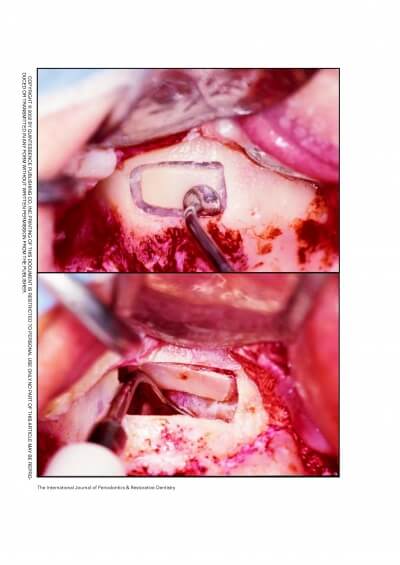

MAXILLARY SINUS AUGMENTATION- 3 CASES

SINUS FLOOR AUGMENTATION WITH HYDROPNEUMATIC TECHNIQUE

SINUS AUGMENTATION PROCEDURES